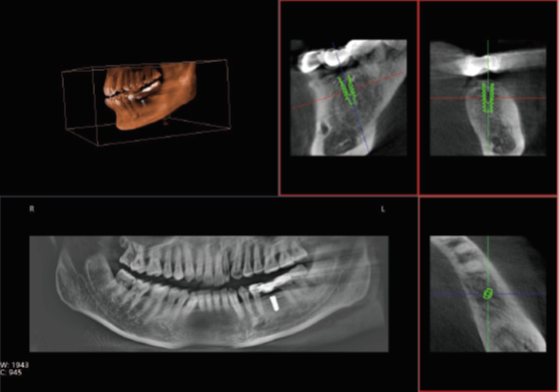

口腔CT是口腔科專用的CT(Cone Beam Computed Tomography), 也就是CBCT,即錐形束CT,采用錐束形X線掃描,可以顯著提高X線利用率,只需圍繞投照體做環(huán)形數(shù)字式投照即可獲取重建所需的全部原始數(shù)據(jù),在計算機中重組,進而獲得三維圖像。通過數(shù)據(jù)采集方式的改進,口腔CT不僅提高了醫(yī)學影像的掃描分辨率,也將放射劑量降低到了一個新的水平。那么,哪些口腔治療會使用到口腔CT呢?

正常情況下,牙齒的排列不在一個平面上, 且具有一定的生理弧度,普通X線往往使圖像相互重疊,使圖片看不清楚。但是,口腔CT的三維成像對牙體、牙根、牙周膜等微細結構顯示更加清晰??梢詭椭t(yī)生了解斷根,牙根內(nèi)吸收、根管鈣化、牙根結石、牙槽骨退縮等情況,能用于根管治療前尋找根管,術后評估根管充填情況,評估牙周炎程度及預期治療效果等。

正畸治療前的診斷分析是治療成功的重要步驟,口腔CT不僅能提供頭顱側位和曲斷片的信息,還可以評價每個牙齒的排列位置,牙根傾斜度,牙槽骨垂直向、頰舌向的骨量,骨密度等。用于牙列不齊矯正、牙頜面畸形矯正、牙周病輔助正畸。